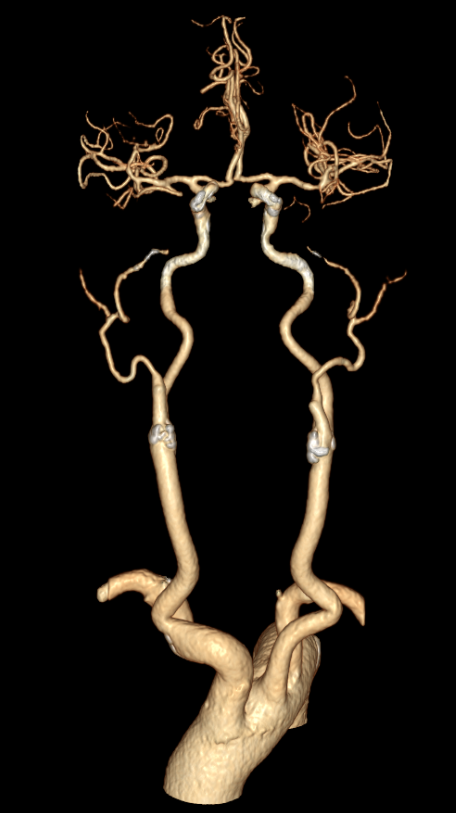

CTA提示右侧大脑中动脉M2段下干闭塞。

动脉长鞘怎么置入有励可说|Locaste 088励楷长鞘及Tarvos微导丝在右侧大脑中动脉M2段取栓术中的应用_https://www.jmylbn.com_新闻资讯_第6张

动脉长鞘怎么置入有励可说|Locaste 088励楷长鞘及Tarvos微导丝在右侧大脑中动脉M2段取栓术中的应用_https://www.jmylbn.com_新闻资讯_第7张

动脉长鞘怎么置入有励可说|Locaste 088励楷长鞘及Tarvos微导丝在右侧大脑中动脉M2段取栓术中的应用_https://www.jmylbn.com_新闻资讯_第8张